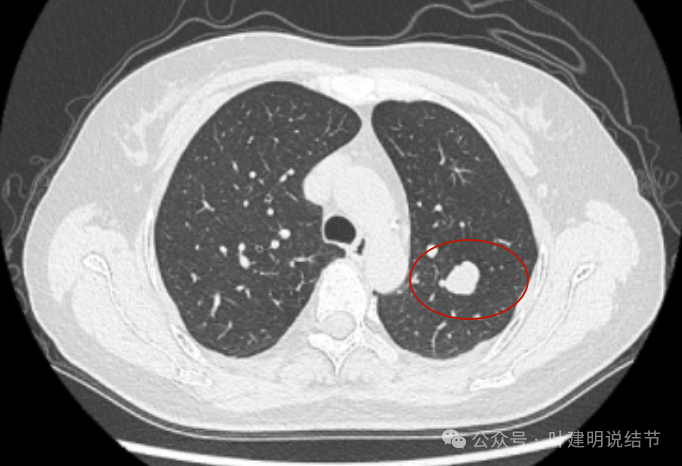

2019年5月时左上叶实性结节,边缘很光滑,没有毛刺或血管征,影像上看像良性的。

2019年10月,变化不大,但这个层面看略显得有膨胀感。